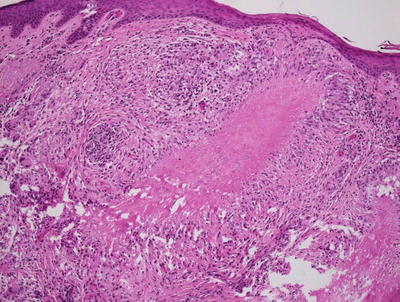

Acne rosacea demonstrates a perifollicular lymphohistiocytic infiltrate with spongiosis at the level of the infundibulum (Fig. 10.13). Sebaceous hyperplasia is present in many cases. Florid cases may have a granulomatous inflammatory response to ruptured follicular epithelium (Figs. 10.14 and 10.15).

Fig. 10.13

Granulomas with multinucleated giant cells located in the region of pilosebaceous units are characteristic of acne rosacea

Fig. 10.14

A caseating granuloma is present in acne rosacea

Fig. 10.15

Granulomas adjacent to follicular units are a diagnostic feature of acne rosacea